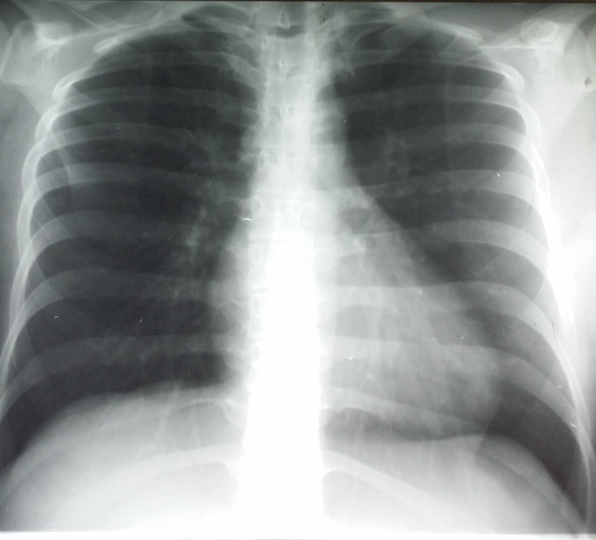

Rx toracică, incidență P-A

DESCRIERE:

la niv. întregului hemitorace stg → opacitate extinsă, nesistematizată, de intensitate mare, omogenă

caracter retractil → tracționează traheea și mediastinul de partea afectată

fără bronhogramă aerică

duce la micșorarea spațiilor intercostale

la niv. hemitoracelui controlateral → hipertransparență compensatorie

DX: atelectazie prin NBP central endobronșic (pe bronhia principală stg)

DD: pleurezie masivă → caracter expansiv